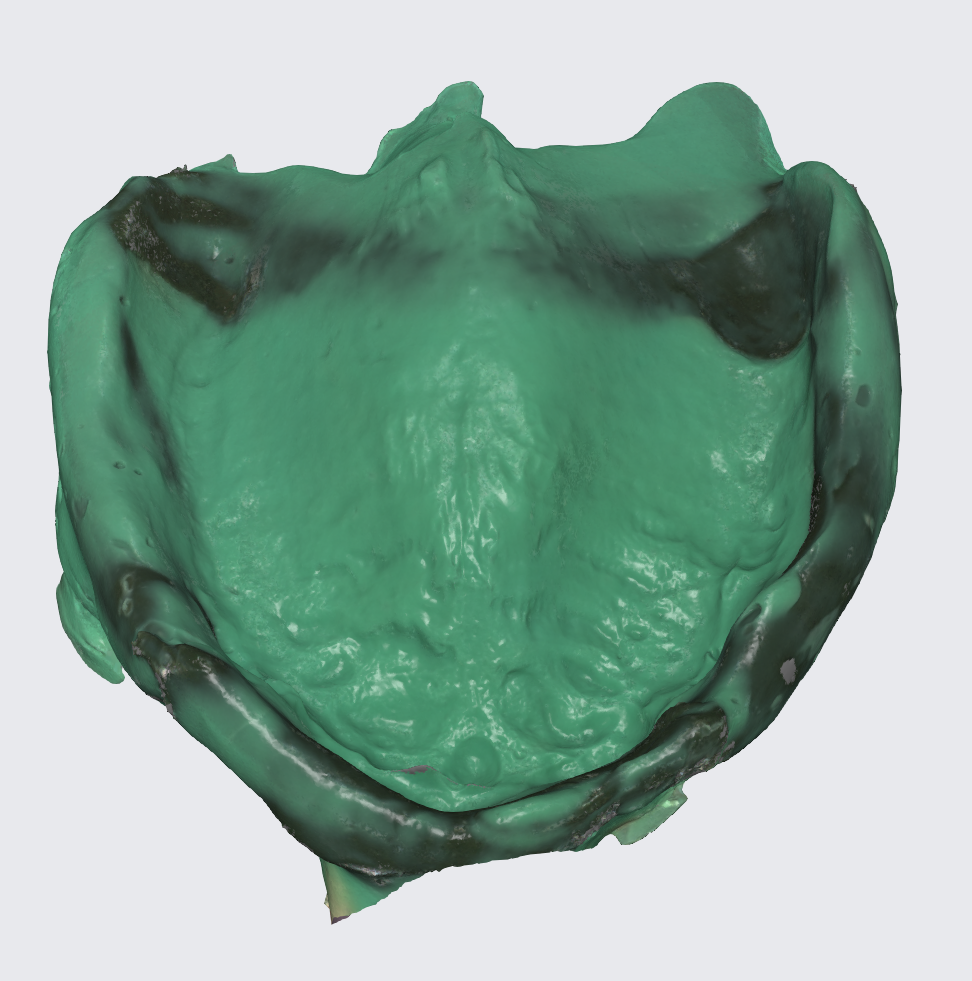

Since the surgeries took place on different appointments we decided to create interim dentures for the patient after each surgery, with the disadvantage that this flow of events would have to maintain the tilted position of the occlusal plane for the time being. For this to happen a scan of the previously operated jaw was performed.

This tray was used for border molding and analog impression and then scanned with a lab scanner as seen in the next photo.